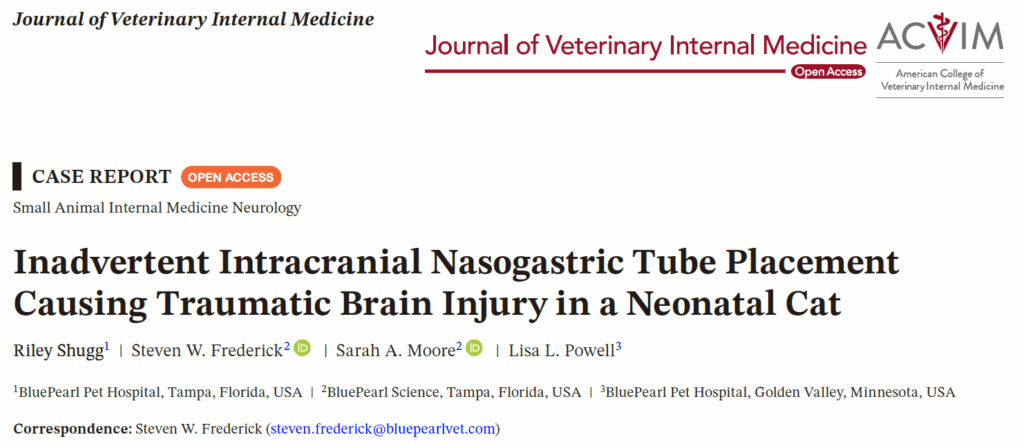

24小时后,再次插入一根3.5 Fr红橡胶鼻胃管,进行了侧位胸部X光检查以确认管子的位置,但导管在食管和胃中缺失。再次进行X光检查,包含头部、颈部和胸部,发现鼻胃管在头内缠绕,强烈怀疑其位于颅内(下图A)。

↑ 鼻胃管通过筛板进入头骨,在后颅窝内卷曲,并重新穿过后颅窝(箭头)。